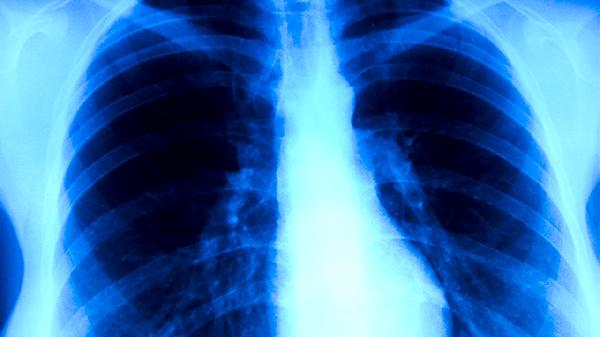

胸部X线检查是肺结核筛查的重要手段,能发现肺部浸润、空洞、纤维化等典型改变。CT检查能更清晰地显示病变细节,对早期病变和肺外结核的诊断价值更高。影像学检查不能单独确诊肺结核,需结合临床表现和其他实验室检查结果。肺结核的影像学表现多样,需与肺炎、肺癌等疾病进行鉴别。